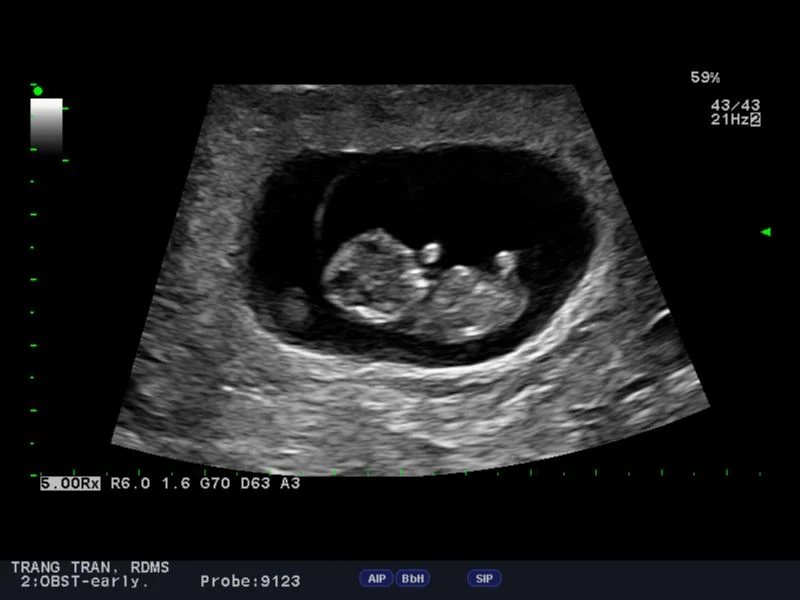

We have already been to two doctor’s visits where we got Ultrasounds and saw the heartbeat. I have to be sure not to take any moment of this child for granted. I will try to go to as many appointments as possible. I will wait to feel that kick for hours if I have to. Harper would kick and Alexa would have me feel her tummy, but then Harper would stop, not wanting to kick her Dada’s hand. I would give up and stop trying to feel it. Not now.